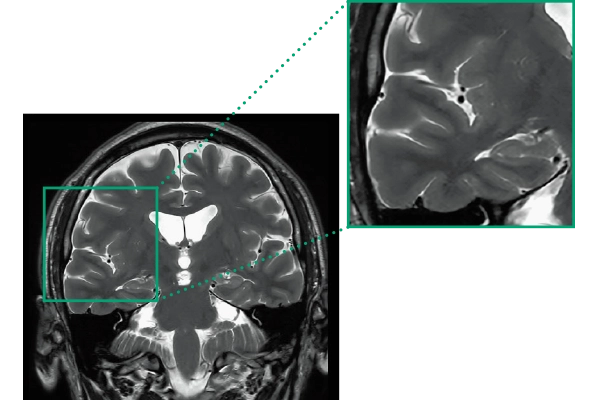

DLR offers 2 options

High Resolution

T2WI, 0.56×0.70×3.0mm, 2:28

ShortScan

FLAIR, 1:14

DWI, 0:36